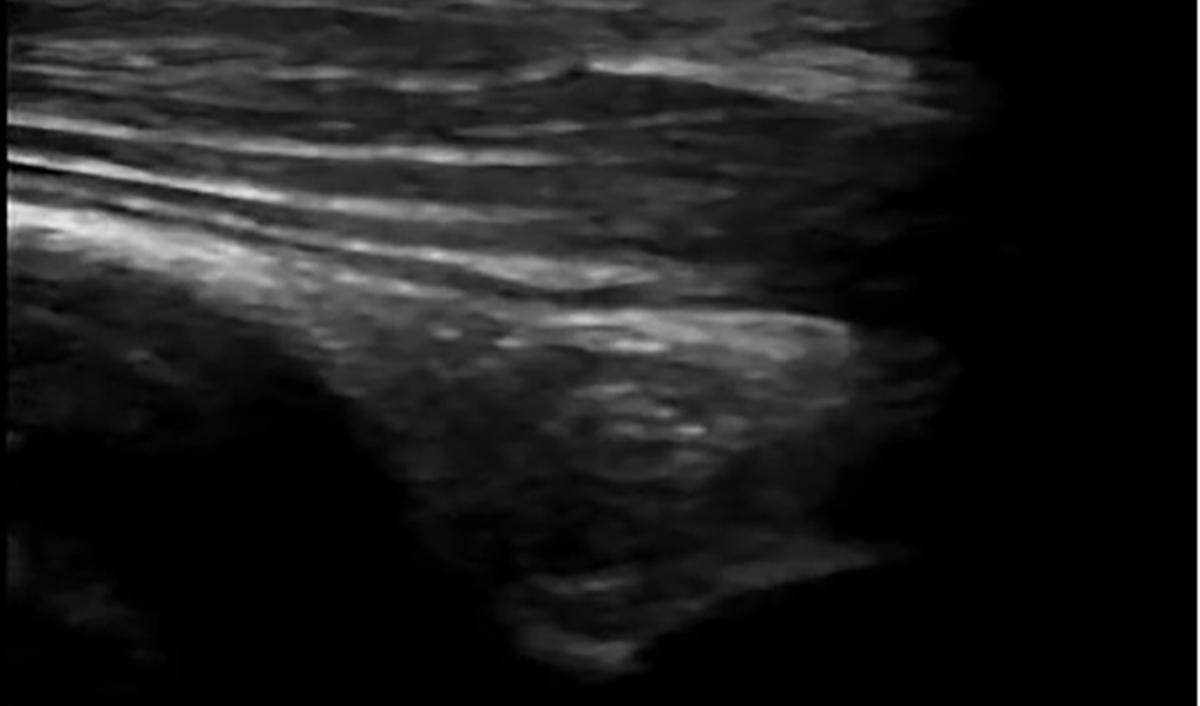

Dr. Artiga’s academic interests include ultrasound, education, and advocacy. Within SAEM RAMS, he has led initiatives such as the Ask-A-Chair educational podcast series, advocacy efforts related to unionization, social media campaigns to promote resident engagement, and the development of board review resources for emergency medicine certification. He has recently taught ultrasound to emergency medicine programs in Latin America.

It was an extremely humbling and eye-opening experience. I went to teach in my father’s country, El Salvador, where I had never visited before. I never truly understood the conditions he lived in beyond his words. All the issues that exist in the U.S. are magnified when you go to countries that don’t have similar resources. Medical decision making is limited by access to resources. It’s not about a lack of capability. I worked with incredibly brilliant doctors who just don’t have access to the same technology or infrastructure we have here. That’s why I believe in supporting ultrasound specifically in these settings. In capable hands, point-ofcare ultrasound can give a clinician life-saving information. Providing this tool and empowering physicians to use it can have a huge impact on individual patients and healthcare systems across the world.

For me, it’s been about chasing my passion and asking, “Who’s on this ride with me?” I’ve always been drawn to ultrasound. Through SAEM’s and the Academy for Emergency Ultrasound’s (AEUS’s) ultrasound didactics and activities, I’ve noticed similar faces showing up. These spaces allow for ideas to connect and develop in ways that don’t happen when you're working alone. You can’t have synergy in isolation. You need people who challenge and inspire you to promote growth. It’s individuals working together, learning from one another, and pushing ideas forward that produce progress.